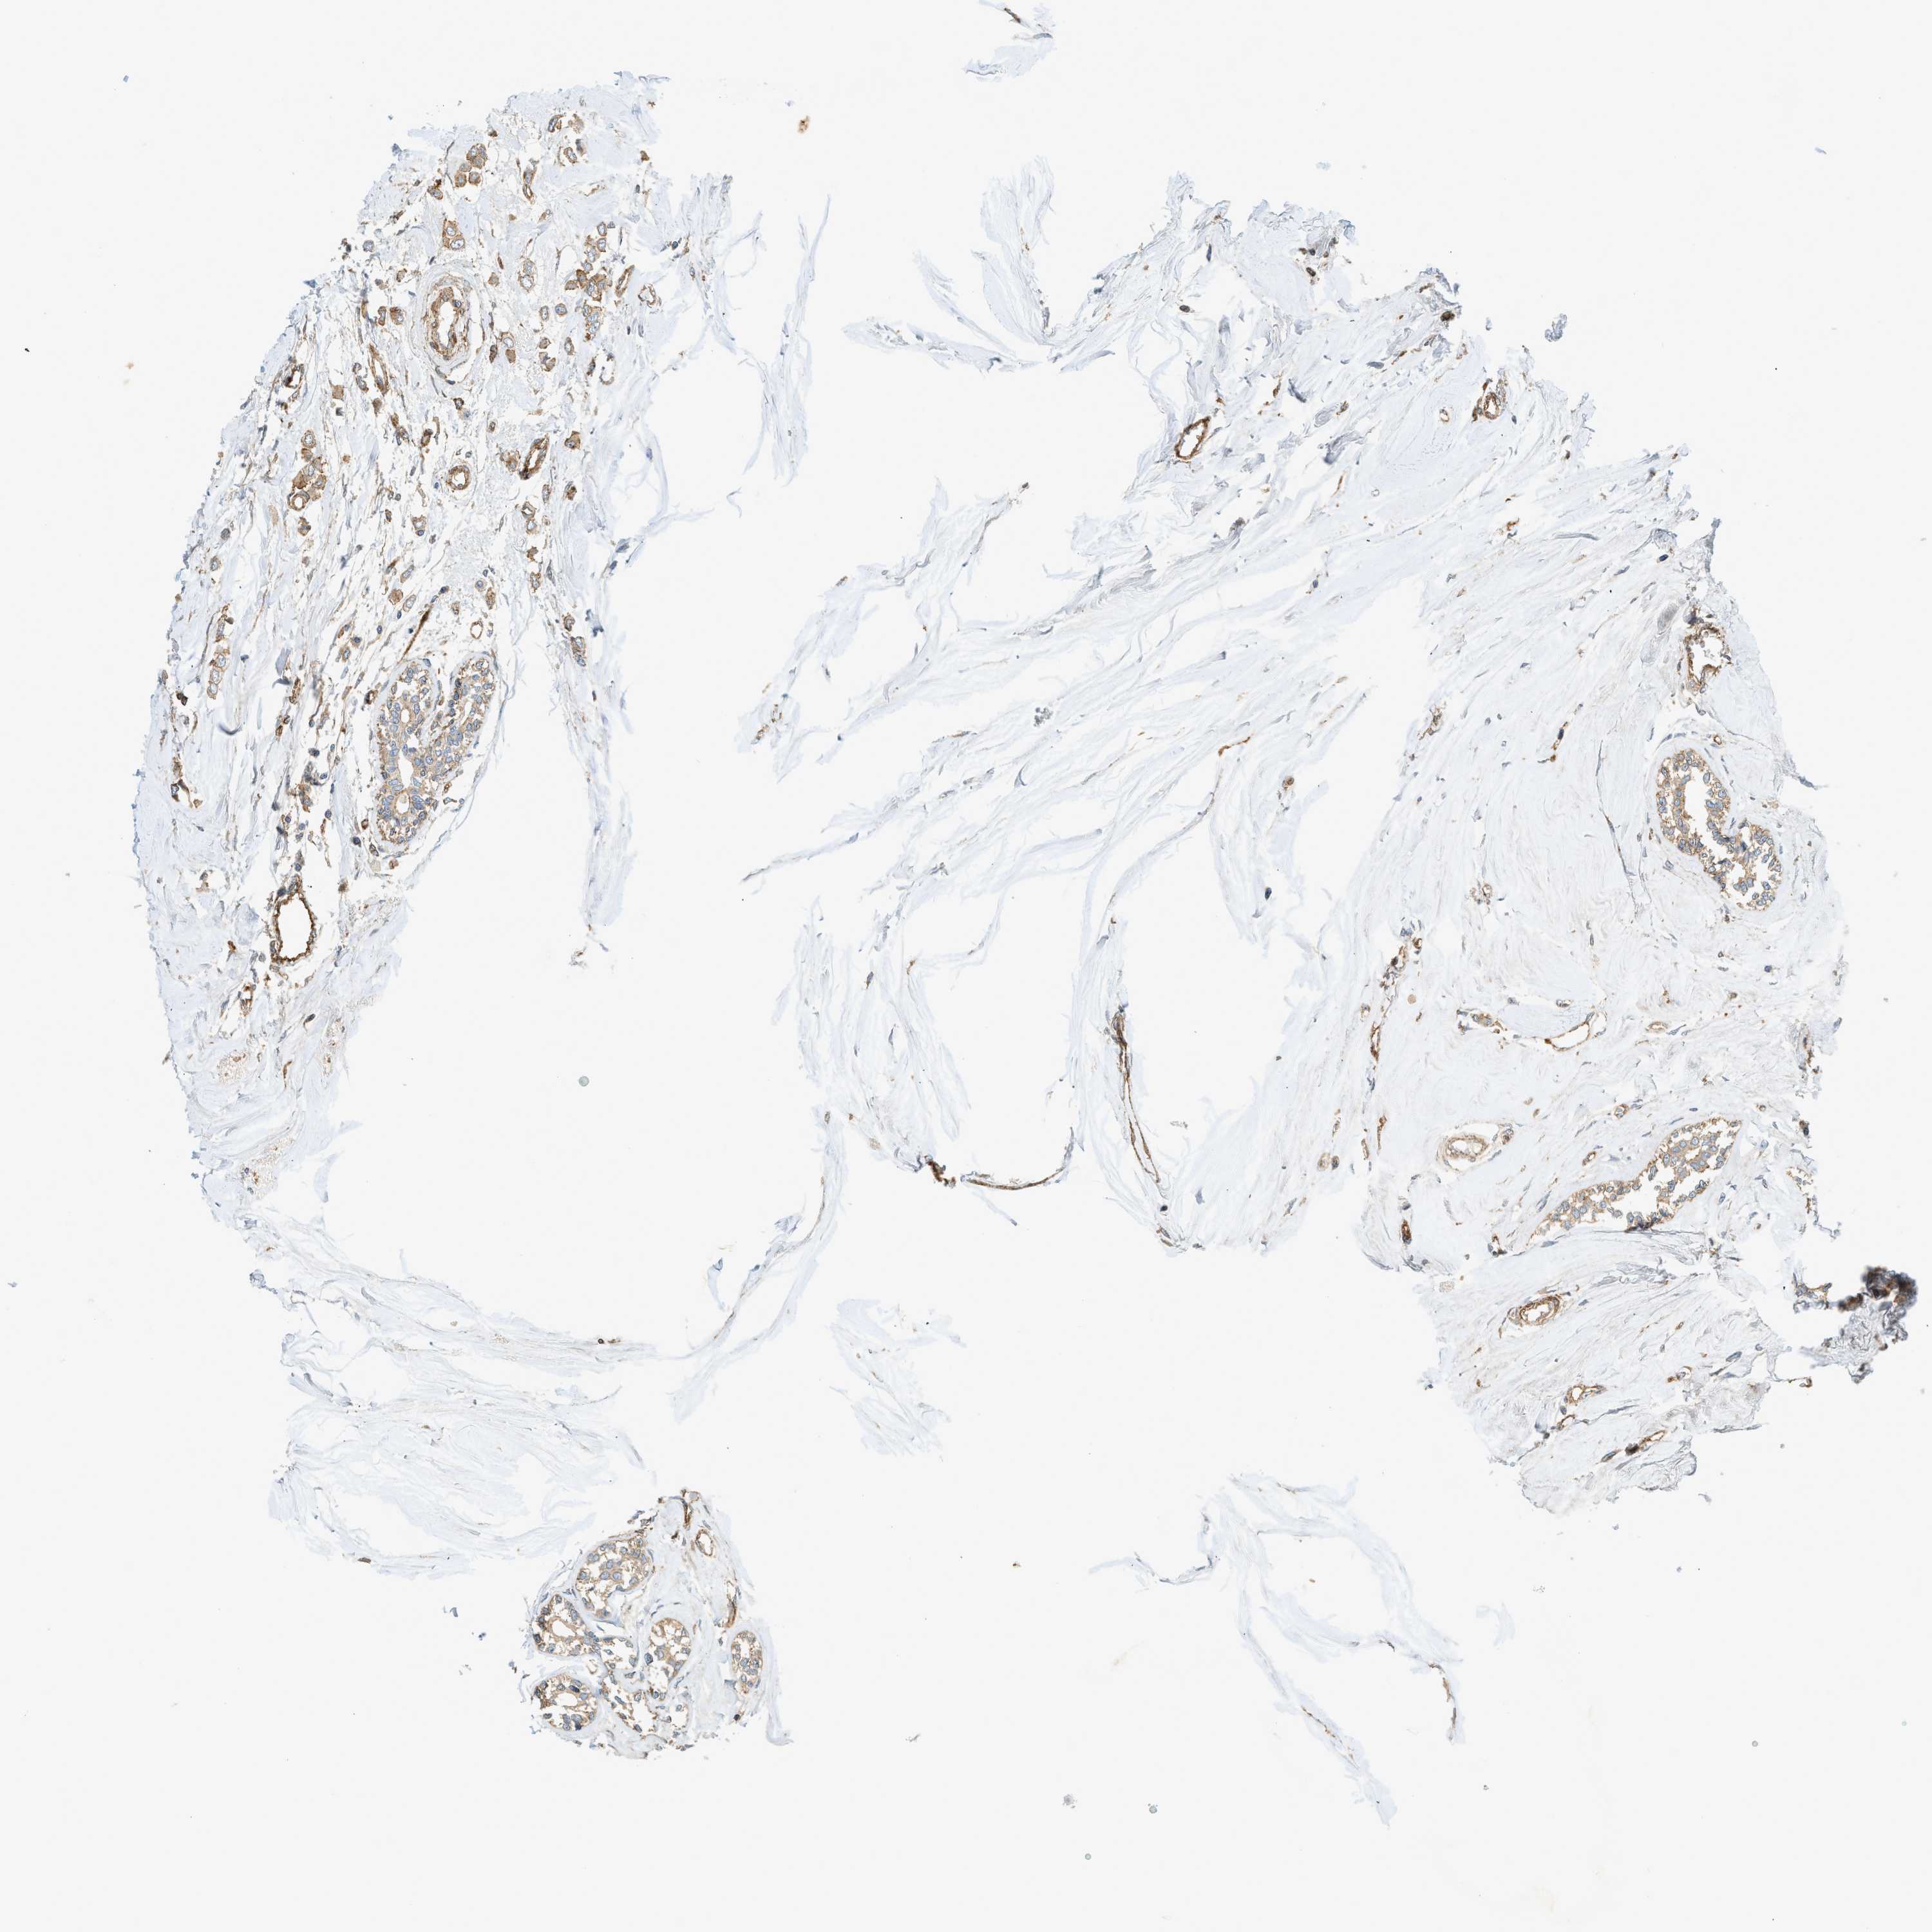

CANCER BREAST CANCER Show tissue menu

BRCA TCGA BRCA VALIDATION PROTEIN EXPRESSION

ANTIBODIES

AND

VALIDATION